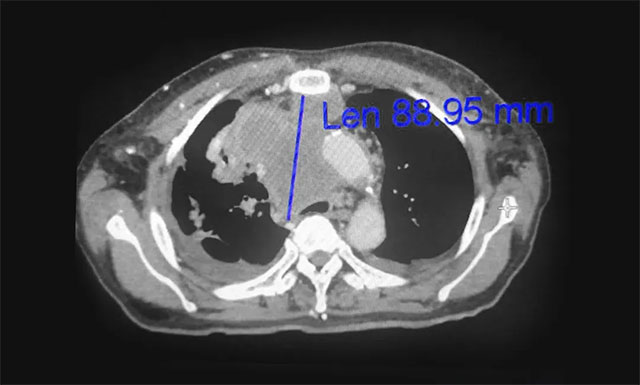

▲ 放疗前